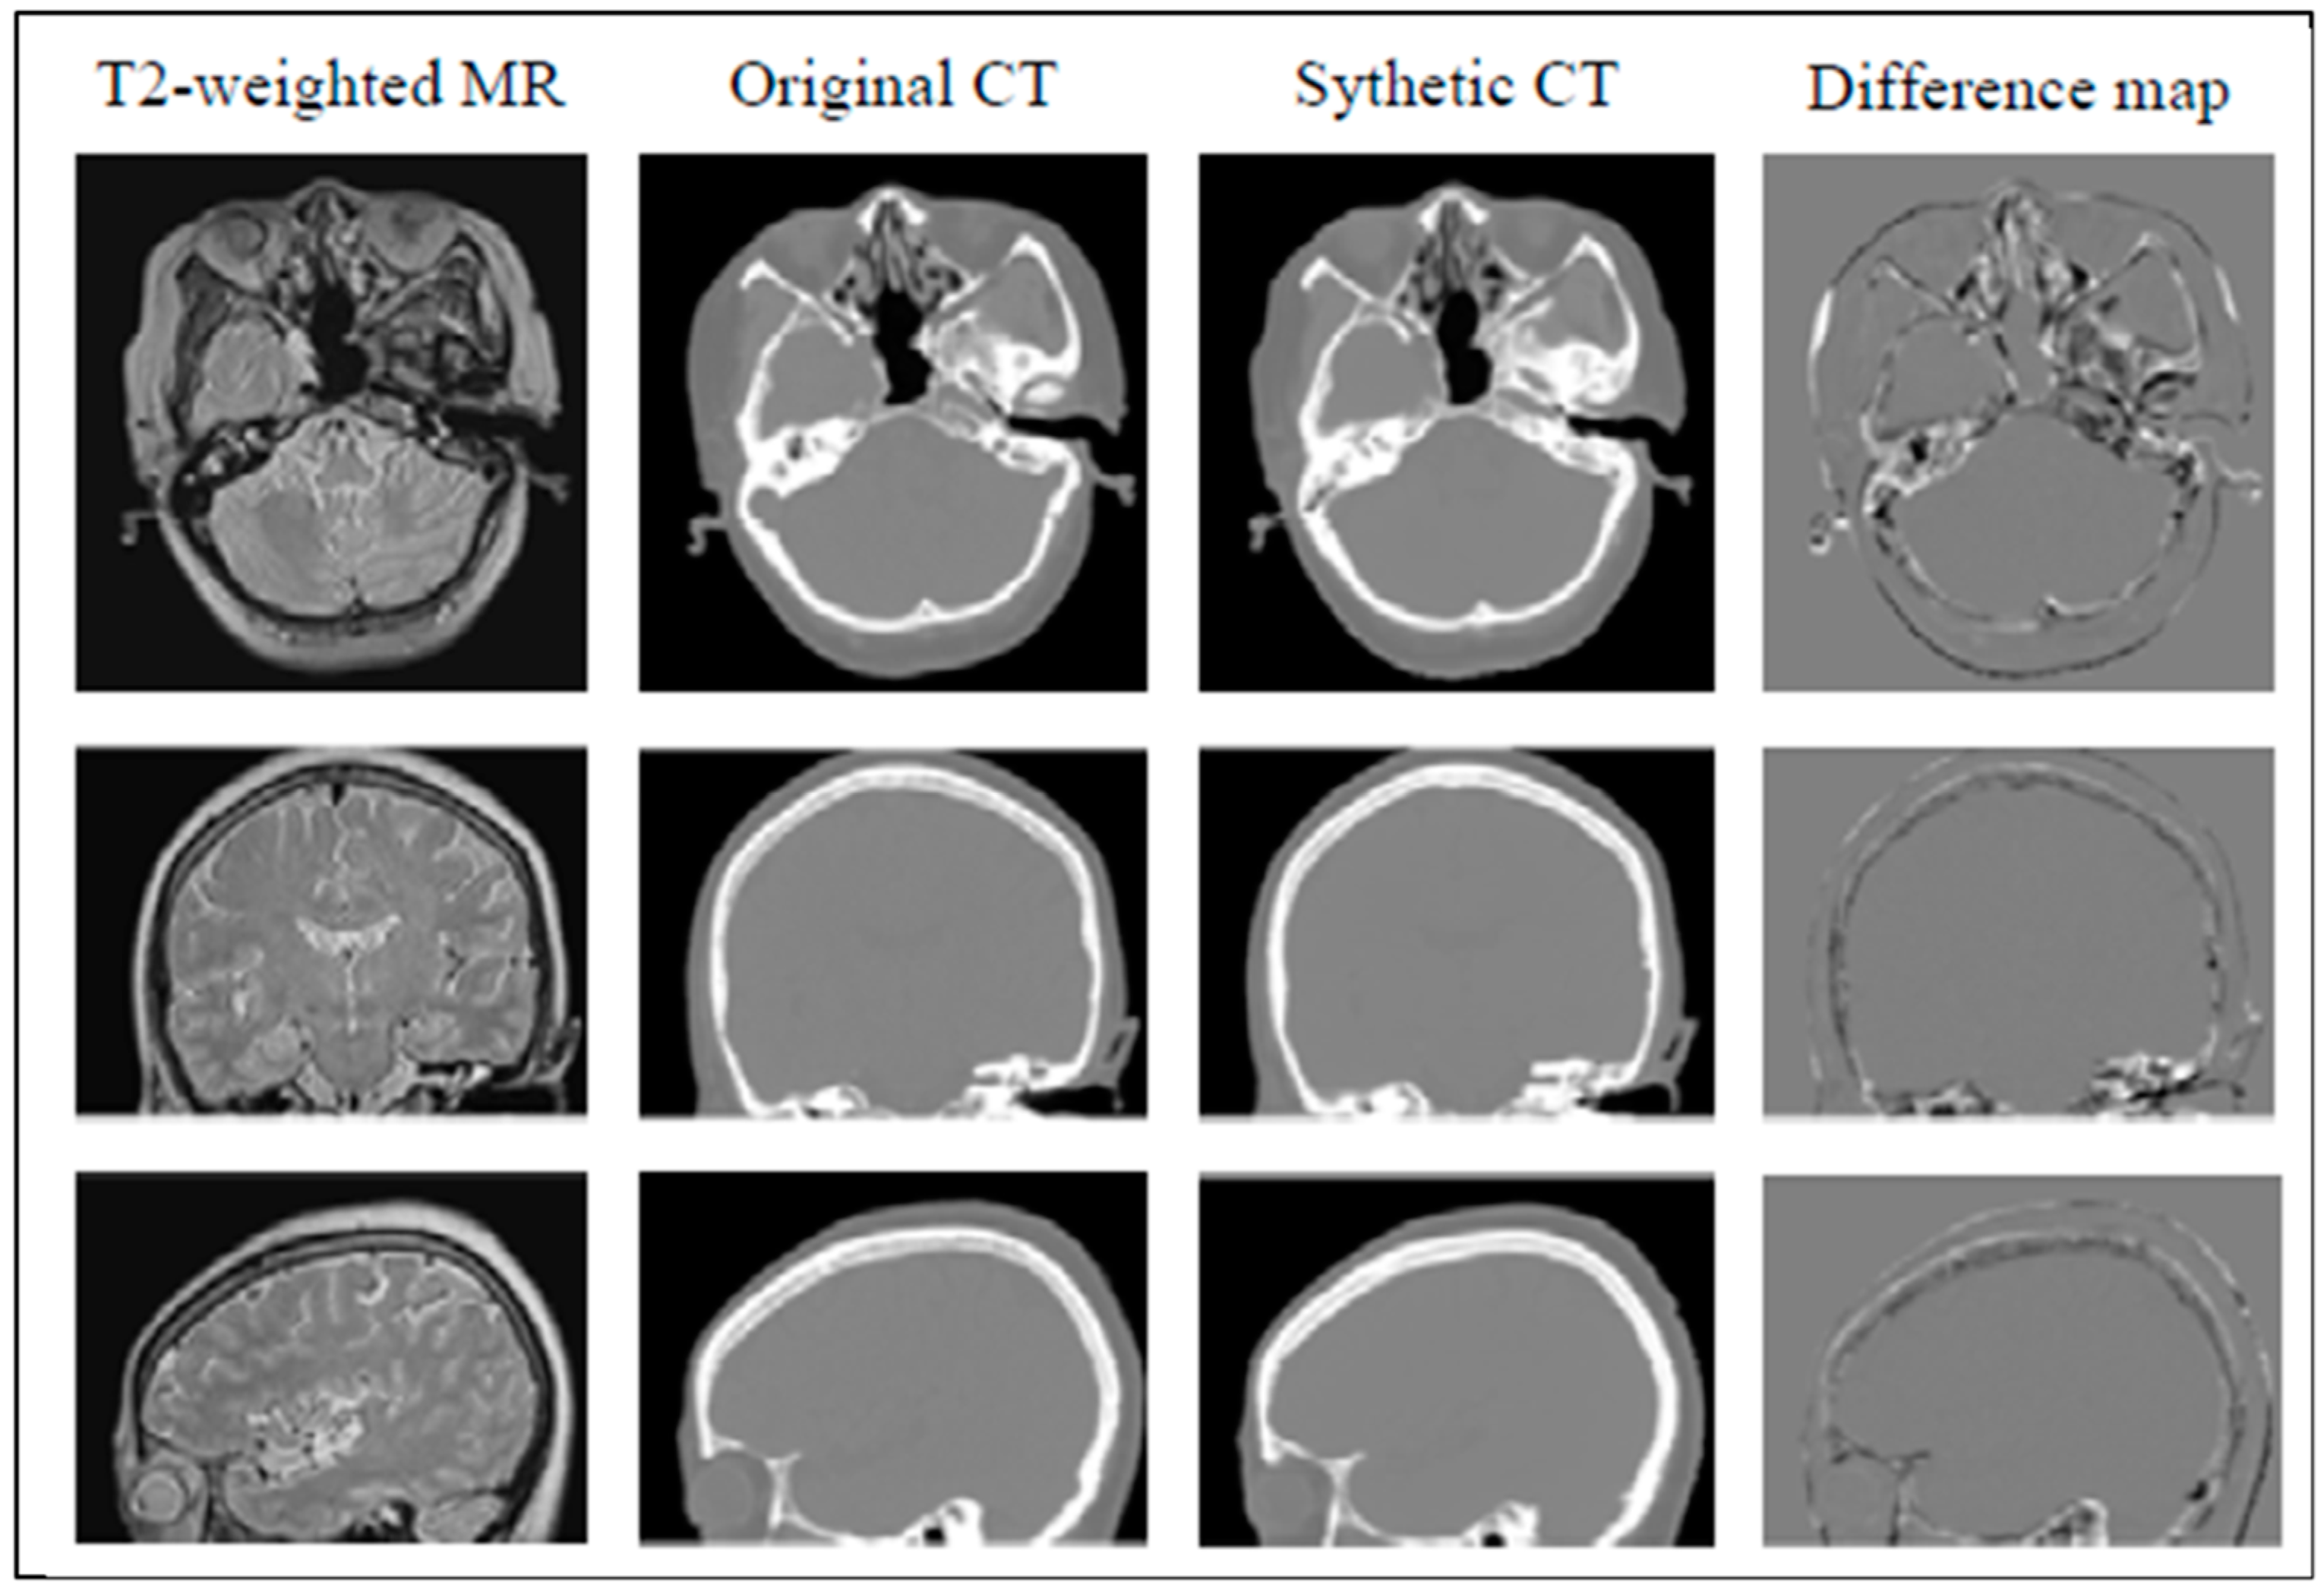

- Bahrami, A.; Karimian, A.; Arabi, H. Comparison of different deep learning architectures for synthetic CT generation from MR images. Phys. Med. PM Int. J. Devoted Appl. Phys. Med. Biol. Off. J. Ital. Assoc. Biomed. Phys. 2021, 90, 99–107. [Google Scholar] [CrossRef] [PubMed]

- Li, Y.; Li, W.; He, P.; Xiong, J.; Xia, J.; Xie, Y. CT synthesis from MRI images based on deep learning methods for MRI-only radiotherapy. In Proceedings of the 2019 International Conference on Medical Imaging Physics and Engineering (ICMIPE), Shenzhen, China, 22–24 November 2019; pp. 1–6. [Google Scholar] [CrossRef]